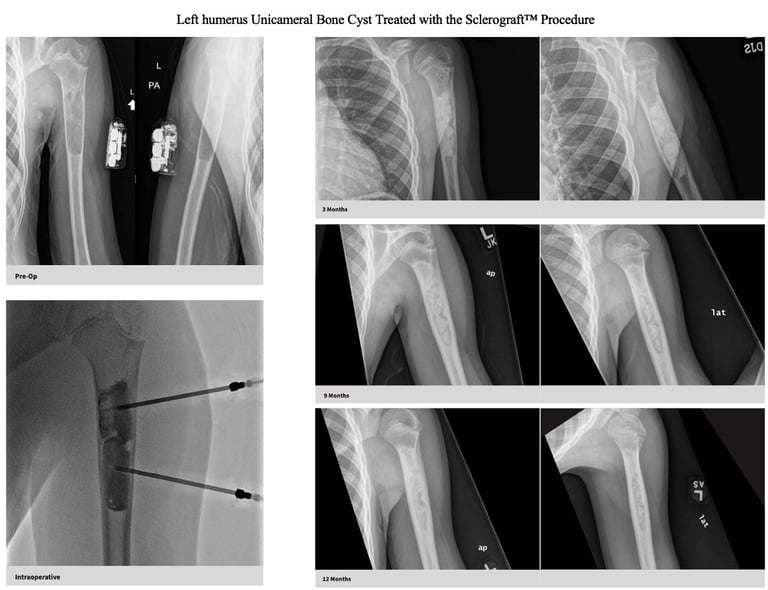

The Sclerograft procedure is a minimally invasive outpatient procedure used to treat bone cysts.

Utilizing needles, chemical sclerosis destroys the cyst wall and regenerative bone graft is injected via the needles to expedite bone healing.

The doctor uses imaging guidance (like X-ray or ultrasound) to guide needles into the cyst.

Chemical sclerosis using chemicals like doxycycline are washed through the cyst to kill the cyst wall lining

Regenerative bone graft is then injected through the needles and the needles are removed. The bone graft is temporary and is eventually reabsorbed by the body.

Gallery

Explore our educational resources and images